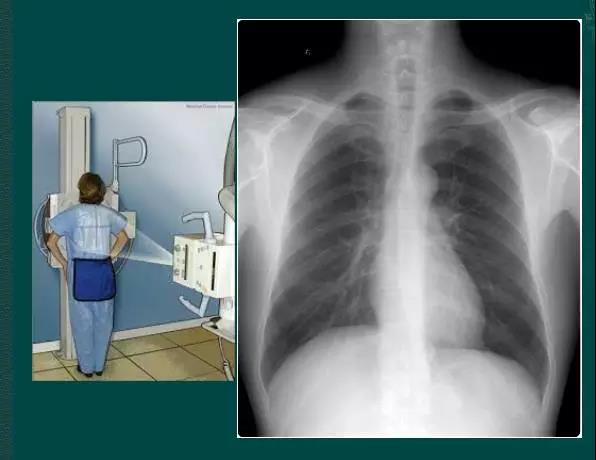

胸部正位片

临床拍标准的胸部正位片其实是后前位片,如上图。

上图为正常胸部后前位片